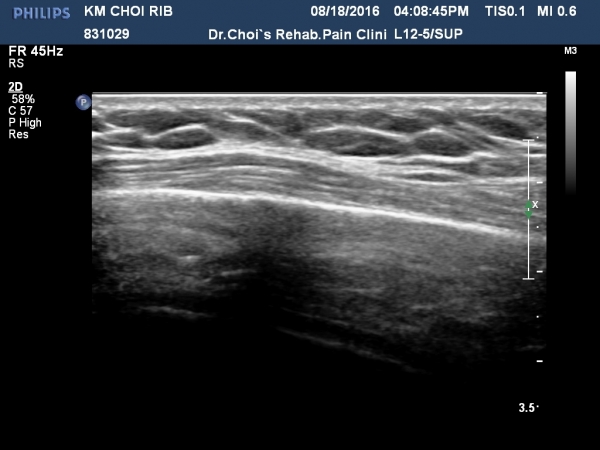

ÃÊÁø ½Ã °¥ºñ»À ÃÊÀ½ÆÄ°Ë»ç¿¡¼­ ÇÇÁú°ñ ¤·³à¼Ó¼º ¼Ò½ÇÀº º¸ÁöÁö ¾ÊÀ¸³ª

±æºñ»À Ç¥Ãþ¿¡ ±¹¼ÒÀûÀÎ ¿¬ºÎÁ¶Á÷ ºÎÁ¾ÀÌ °üÂûµÈ´Ù(»çÁø 1, 2, 3, 4).